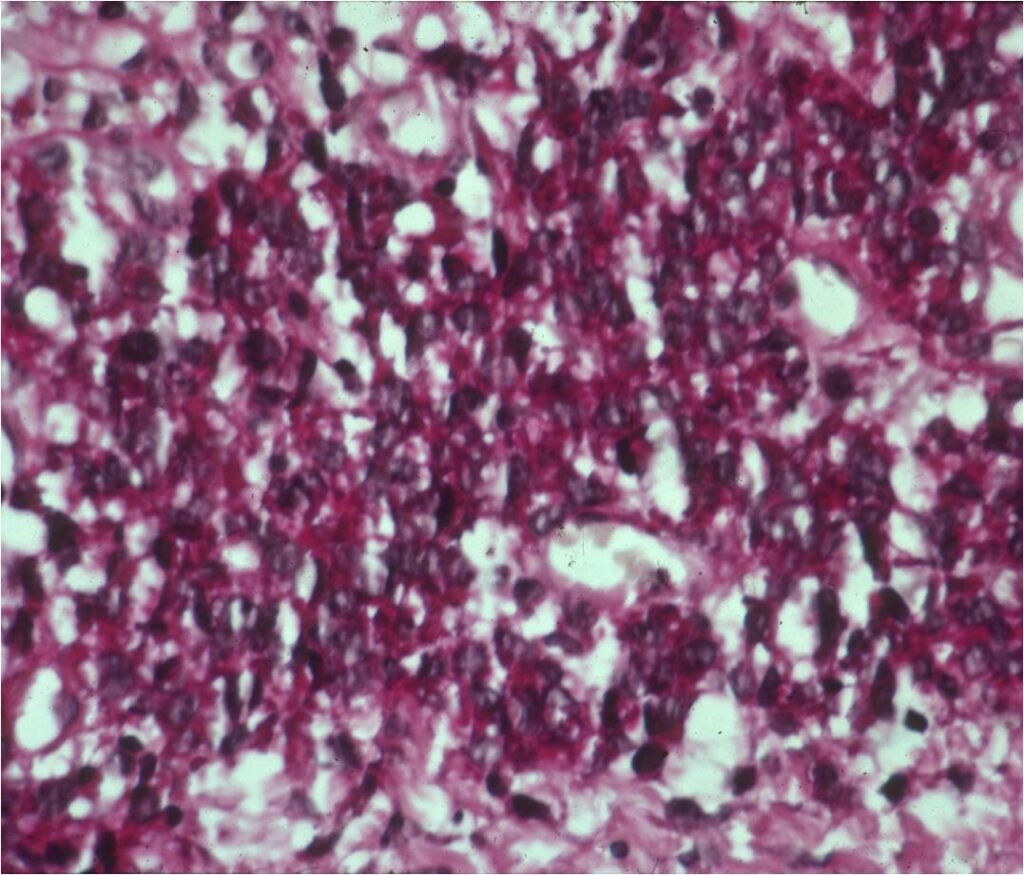

Microscopic Pathology

- Ewing sarcoma is composed of undifferentiated, small round, polygonal mesenchymal cells rich in glycogen

- Sheets of uniform cells with scanty pale cytoplasm and indistinct cell boarders

- No Matrix

- Nuclei are round/oval with finely dispersed chromatin

- Virtually no cytoplasm

- Areas of necrosis

- Variable number of mitoses

- Cells are similar in appearance

- Geographic necrosis with perivascular sparing

- PAS (glycogen positive); Reticulin stain poor

- Immunostains: Vimentin (+), CD99 (+); Leukocyte Antigen Negative

- Overexpress MIC2 detected by CD99

Small Round Blue Cells No Matrix Large Nuclei No Cytoplasm